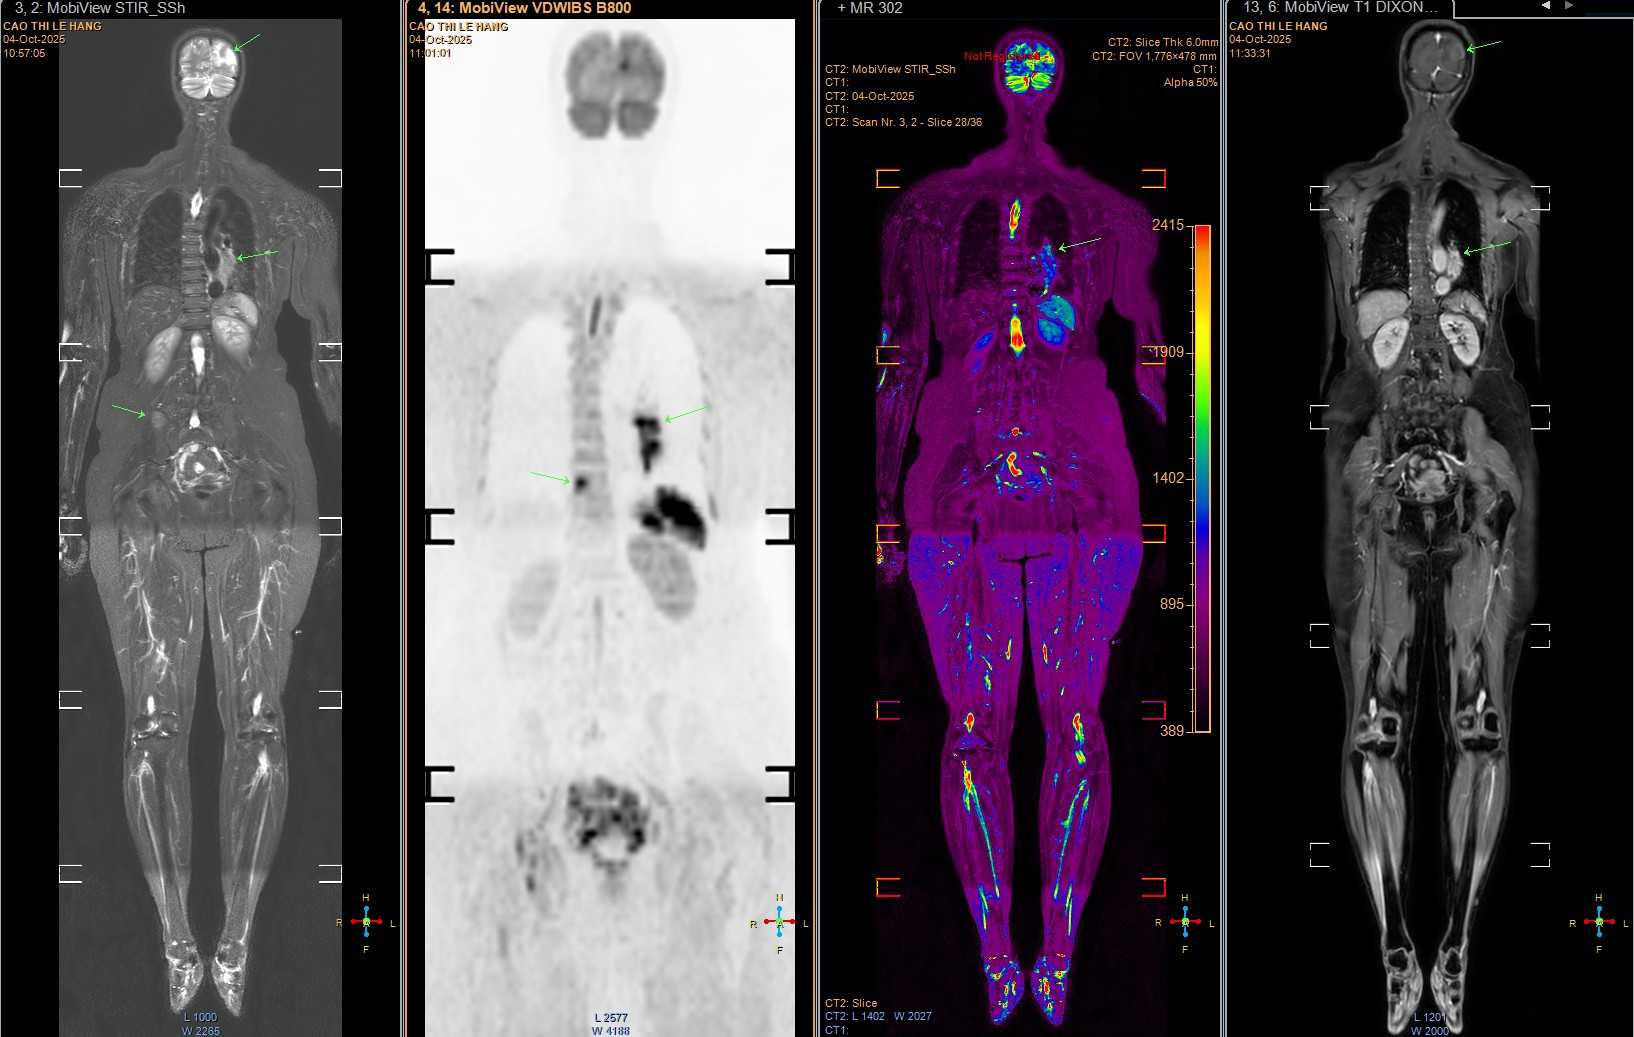

Qua chụp MRI sọ não, bác sĩ phát hiện bệnh nhân có nhiều ổ tổn thương di căn dạng biểu mô tuyến. Nghi ngờ di căn từ phổi hoặc đại tràng, bà được chụp CT phổi và phát hiện khối u ung thư phổi lớn ở đáy phổi trái. Đáng tiếc, ung thư đã di căn lên não, cột sống và xương chậu, tiên lượng xấu.

Giáo sư Khoa lo ngại về tỷ lệ thanh thiếu niên sử dụng thuốc lá và thuốc lá mới (như thuốc lá điện tử) vẫn ở mức cao, làm gia tăng nguy cơ ung thư phổi trong tương lai. Ông khuyến nghị tầm soát sớm cho những người có nguy cơ cao, như người hút thuốc chủ động hoặc thụ động. Chụp CT liều thấp có thể phát hiện tổn thương nhỏ, trong khi các kỹ thuật hiện đại như PET/CT, PET/MRI, kết hợp sinh học phân tử, giúp xác định đột biến gene và lựa chọn điều trị trúng đích hiệu quả.